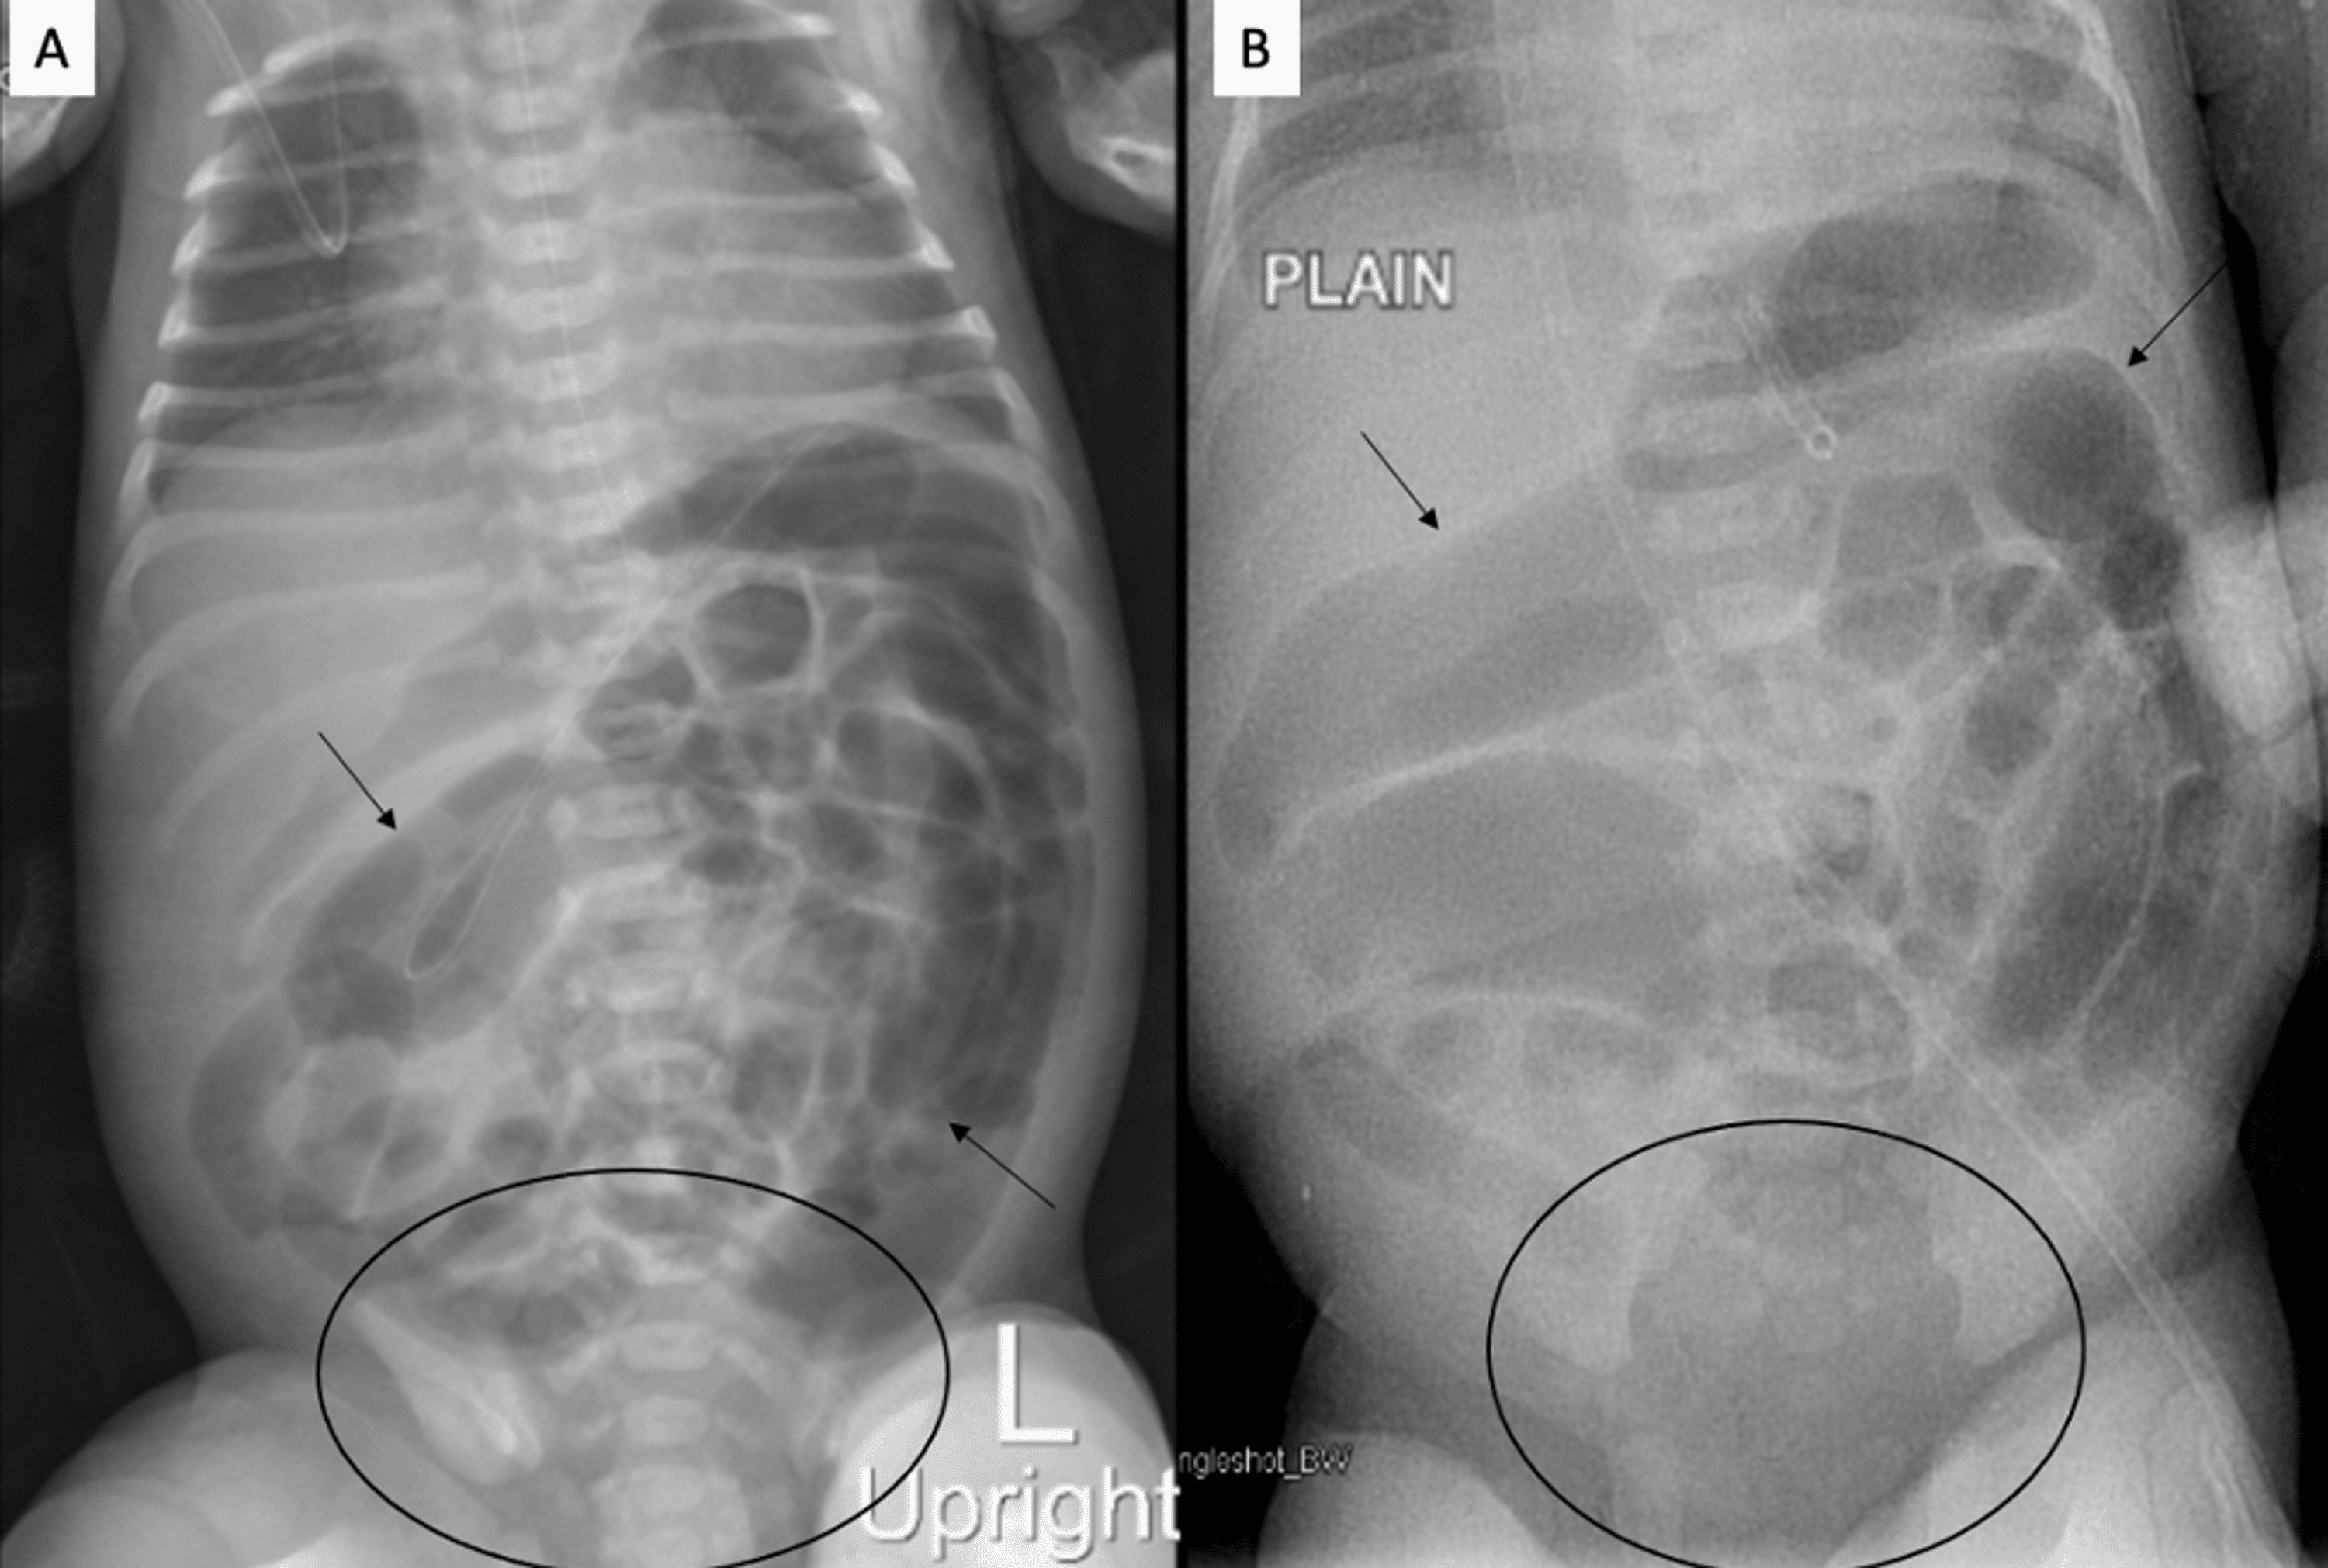

From www.cureus.com

Windsock or Cobra Head Sign A Distinctive Imaging Sign to White Stool In Neonates It is critical to detect. White poop can indicate that your baby isn’t producing enough bile in their liver to help them digest food properly. How do you approach the concern of “blood in. Biliary atresia is a rare disease of the liver and bile ducts that occurs in infants. Uncommon in term neonates, but can occur. Jaundice (yellowing of. White Stool In Neonates.